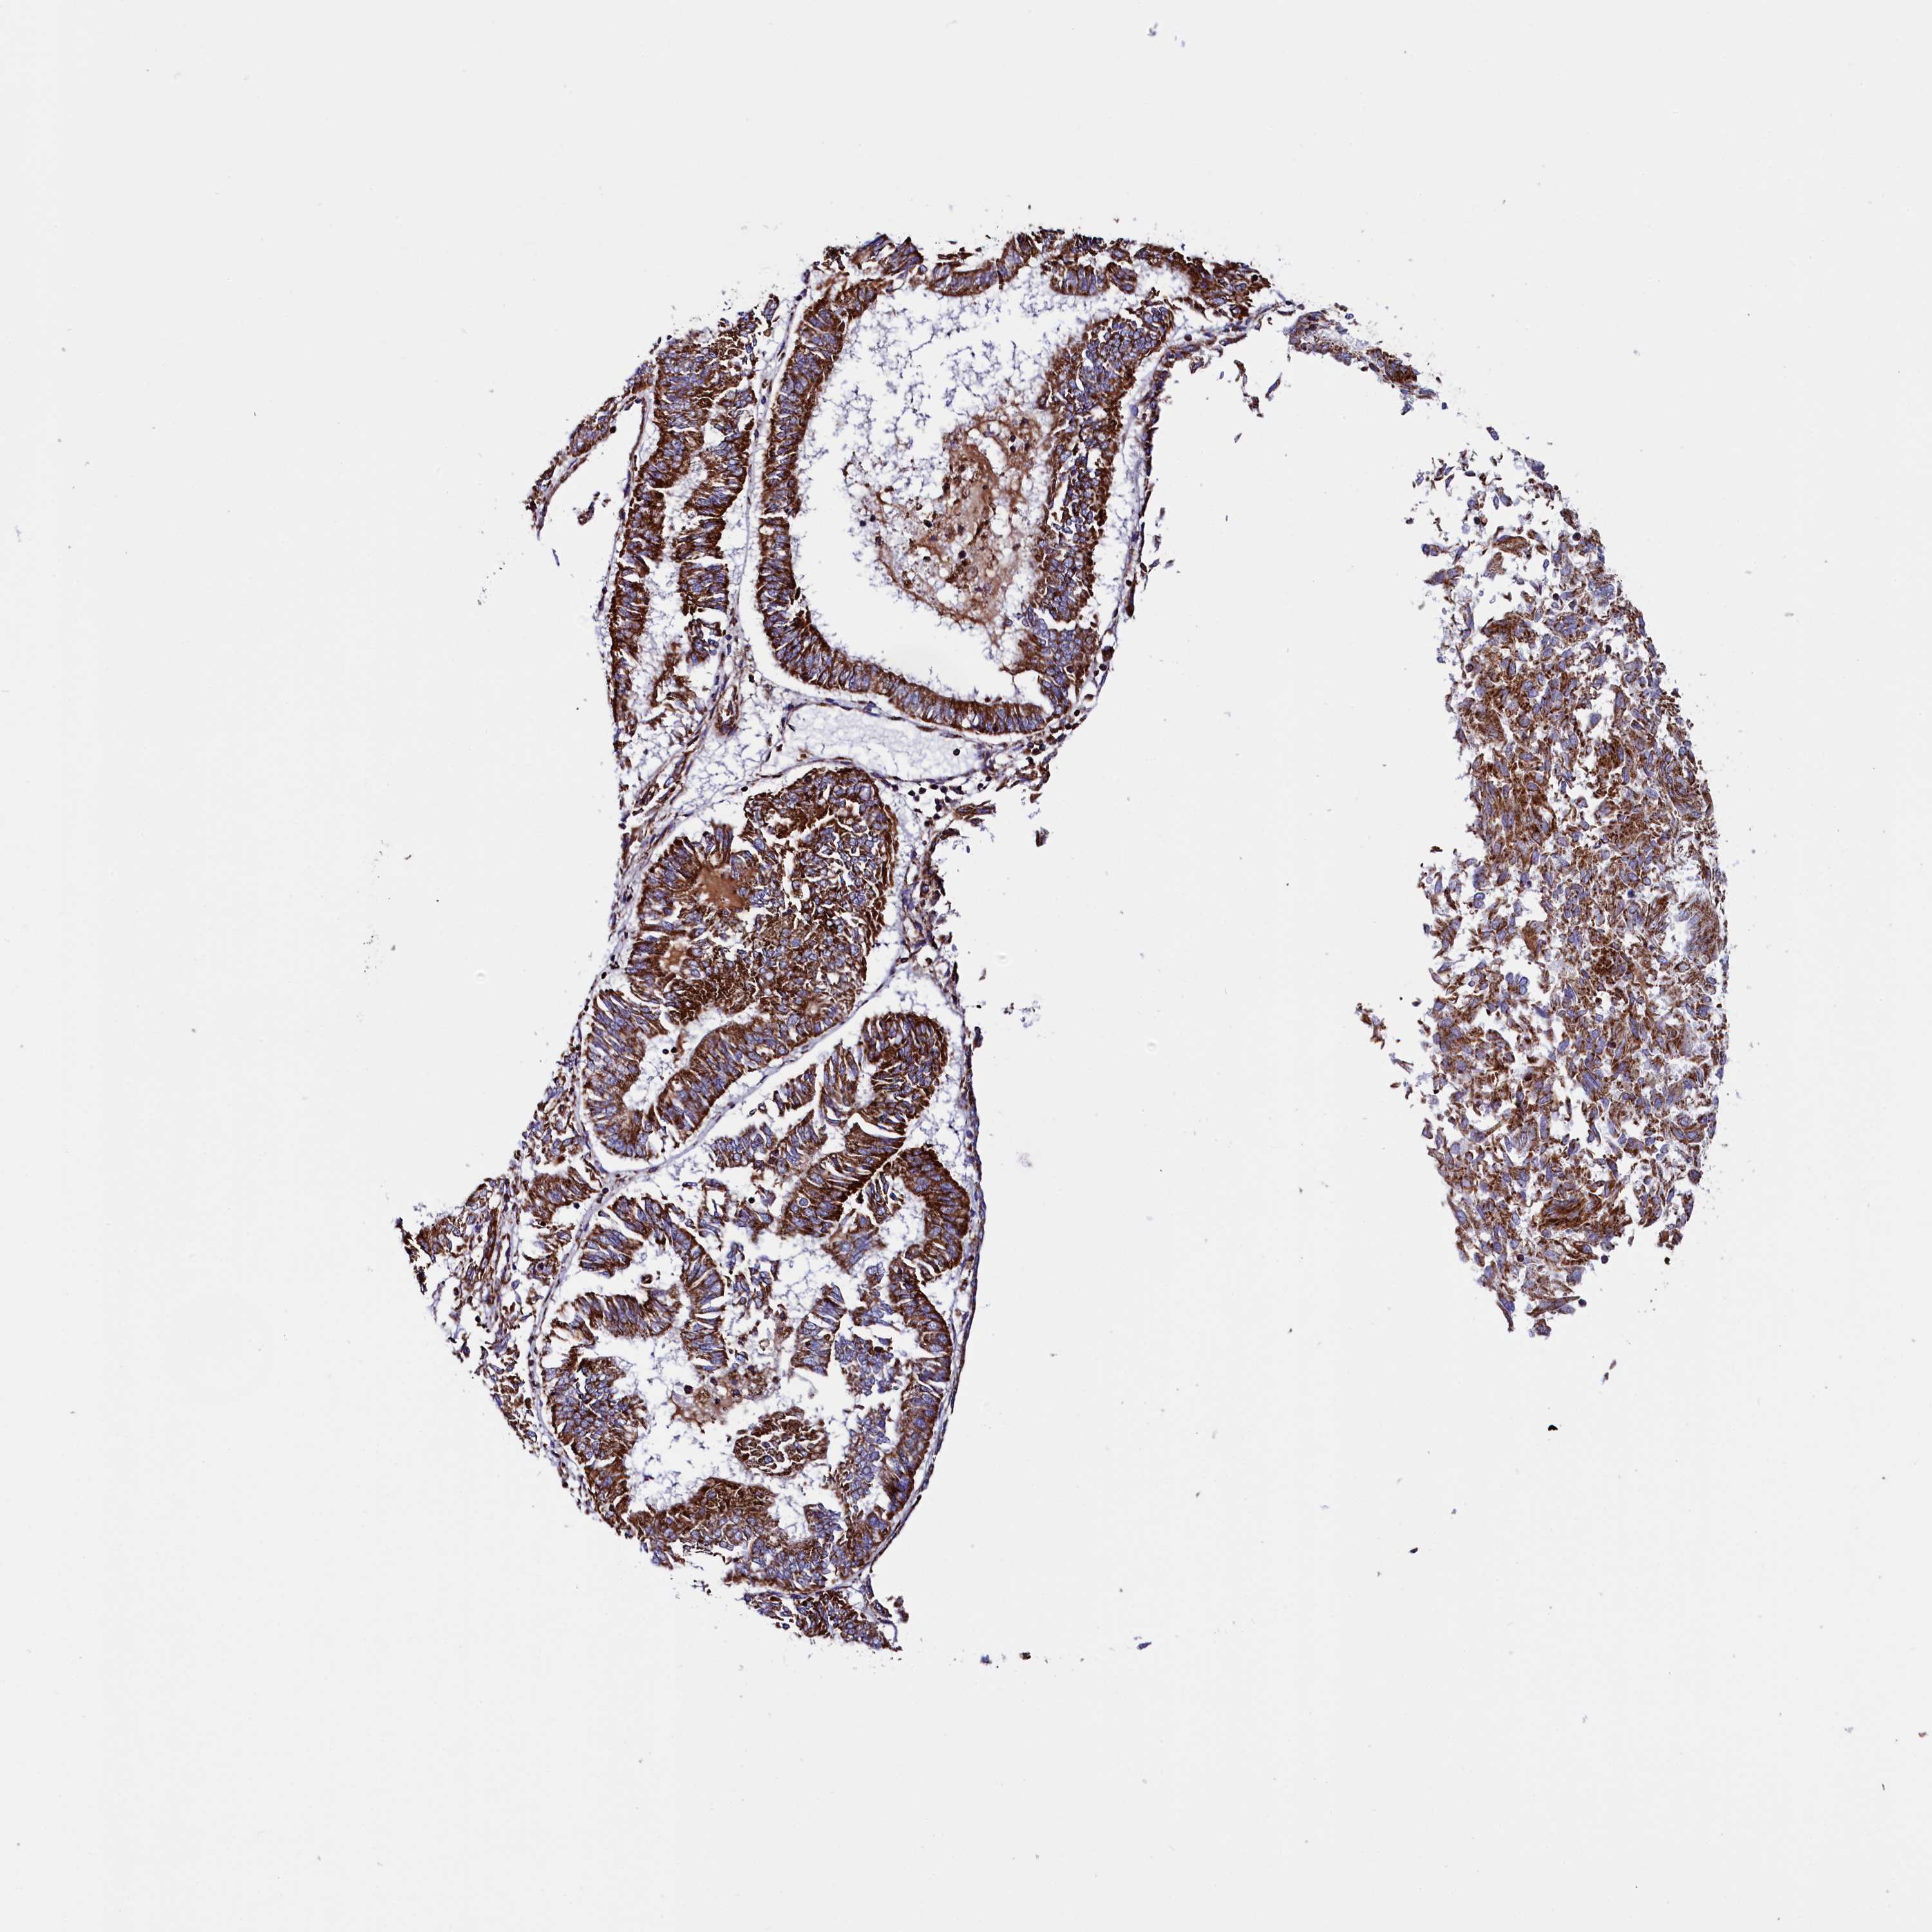

ENDOMETRIAL CANCER - Protein expressioni

A mouse-over function shows sample information and annotation data. Click on an image to view it in a full screen mode. Samples can be filtered based on level of antibody staining by selecting one or several of the following categories: high, medium, low and not detected. The assay and annotation is described here.

Note that samples used for immunohistochemistry by the Human Protein Atlas do not correspond to samples in the TCGA dataset.

Antibody stainingi

Antibody staining in the annotated cell types in the current human tissue is reported as not detected, low, medium, or high, based on conventional immunohistochemistry profiling in selected tissues. This score is based on the combination of the staining intensity and fraction of stained cells.

Each image is clickable and will lead to virtual microscopy that enables deeper exploration of all samples and also displays staining intensity scores, fraction scores and subcellular localization as well as patient and tissue information for each sample.

Antibody HPA042139

Antibody HPA058526

Staining

High

Medium

Low

Not detected

Intensity

Strong

Moderate

Weak

Negative

Quantity

>75%

75%-25%

<25%

None

Location

Nuclear

Cytoplasmic/membranous

Cytoplasmic/membranous,nuclear

Adenocarcinoma, NOS

Carcinoma, NOS